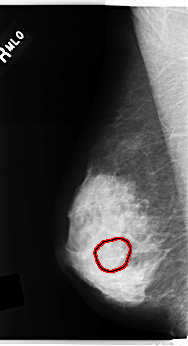

C_0284_1.RIGHT_MLO

RIGHT_MLO LINES 4840 PIXELS_PER_LINE 2632 BITS_PER_PIXEL 12 RESOLUTION 50 OVERLAY

FILE: C_0284_1.RIGHT_MLO.OVERLAY

TOTAL_ABNORMALITIES 1

ABNORMALITY 1

LESION_TYPE MASS SHAPE OVAL MARGINS OBSCURED

ASSESSMENT 3

SUBTLETY 4

PATHOLOGY BENIGN

TOTAL_OUTLINES 1